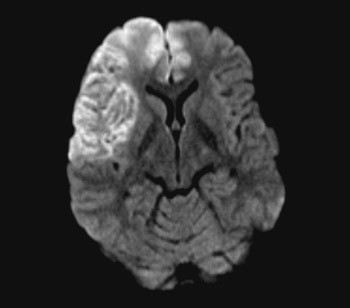

En person i 20-årene med kjent migrene med aura fikk infarkter i høyre arteria cerebri media og begge anteriorgebet (figur 1 viser en magnettomografidiffusjonsvektet serie). Cerebral computer- og magnettomografi med blodstrømsangiografi (MRA) etter innleggelse viste upåfallende strømning uten tegn til disseksjon eller vaskulitt. Hemikraniektomi ble nødvendig etter utvikling av malignt hjerneødem. MR-angiografi i narkose dagen etter operasjonen viste åpne arterier (figur 2 viser en åpen carotistopp (hvit pil), normal basilaristopp (rød pil) samt en ikke-lukket Willis’ sirkel, som er en anatomisk normalvariant (stjerner)). Testing på sentralstimulerende substanser, antikardiolipin, antinukleære antistoffer, nevronantistoffer og tumormarkører ga negative funn. Transøsofageal ekkokardiografi viste et minimalt patent foramen ovale, lite sannsynlig relatert til hendelsen, ifølge kardiolog. Pasienten utviklet alvorlig hjernestammeaffeksjon og MR-angiografi viste forsnevring i arteria basilaris posterior-forgreningen (pilene i figur 3). Arterielle karspasmer ble retrospektivt mistenkt. Den første mistenkte karspasmen i høyre media-/anteriorforgreningen forble udokumentert. Den andre i basilaris-/posteriorforgreningen ble dokumentert postoperativt (pilene i figur 3). Bildene av flere nytilkomne infarkter i bakre kretsløp vises ikke. Tre uker etter hemikraniektomi var ny angiografi normalisert (figur 4).